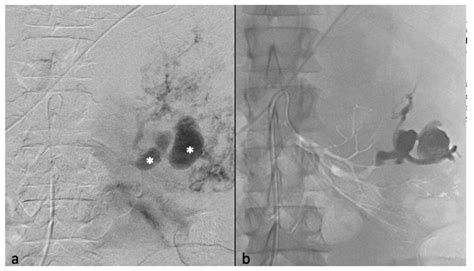

• Selective Arterial Embolization (SAE): A minimally invasive procedure where doctors inject substances into the blood vessels feeding the tumor to “starve” it and reduce its size, effectively minimizing the risk of future bleeding.